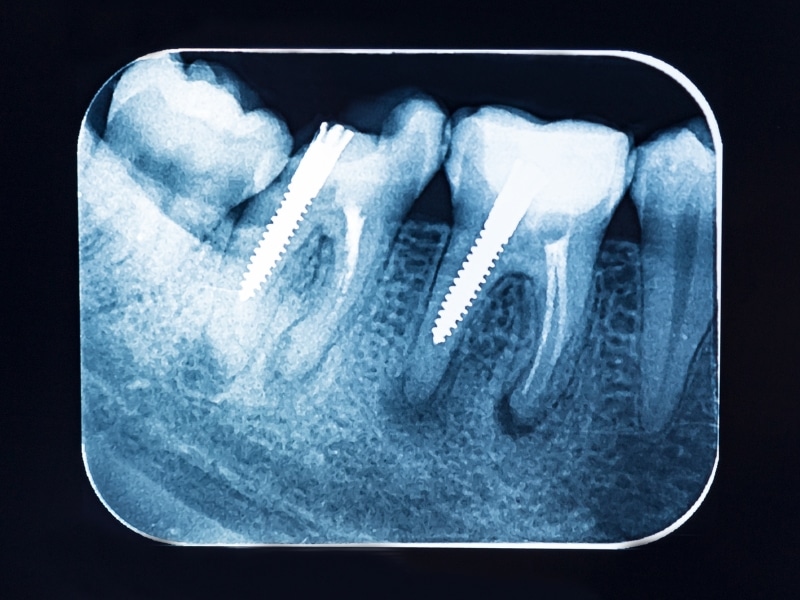

- Periapical X-rays: These go deep, showing the full tooth from top to root, plus the surrounding bone. Ideal for root issues.

- Panoramic X-rays: This one takes a wide shot — your whole jaw, all at once. It’s used for wisdom teeth, jaw structure, implants, and braces planning.

- Digital sensors: Provide sharper images and lower radiation than older film — and they’re quicker to process.